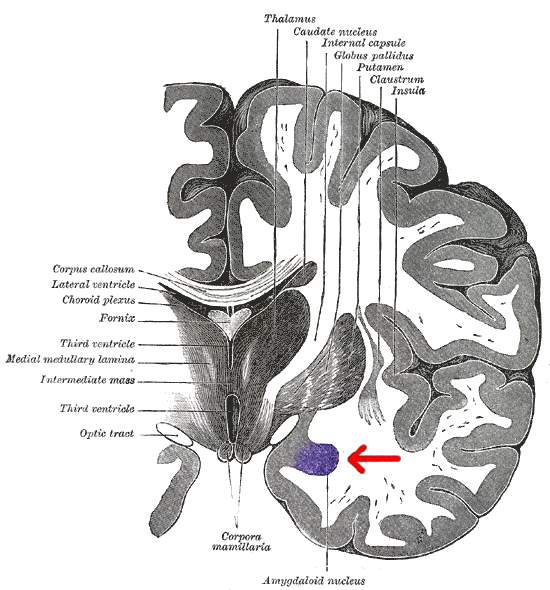

편도체는 뇌의 측두엽에 위치한 아몬드 모양의 구조로, 12개 이상의 신경핵을 포함하며 다양한 뇌 영역과 연결되어 있다. 해부학적으로는 외측핵, 중심핵, 내측핵 등으로 나뉘며, 기저핵의 일부로 간주되기도 한다. 편도체는 정서 처리, 특히 공포와 같은 부정적인 감정을 처리하고, 공포 기억 형성에 중요한 역할을 한다. 또한 정서 학습, 기억 조절, 사회적 행동, 공격성 등 다양한 기능과 관련이 있으며, 불안 장애, 우울증, 자폐증 등 정신 질환과의 연관성도 연구되고 있다. 최근 연구에서는 성적 지향과 편도체의 구조적 차이 간의 상관관계가 제시되기도 한다.

편도체는 해부학적으로 구별되는 여러 핵[6]들의 집합체로, 12개가 넘는 핵이 확인되었다.[7] 이들 핵은 각각 고유한 세부 구조와 뇌의 다른 부분과의 구별되는 연결망을 가지고 있다.[7] 주요 핵 그룹으로는 측측 복합체, 중심핵, 피질핵, 내측핵, 그리고 중간세포 집합체 등이 있다.[4][102]

편도체는 여러 개의 핵[6]으로 구성된 복합체이며, 12개가 넘는 핵이 확인되었다.[7] 각 핵은 고유한 세부 구조를 가지며 뇌의 다른 부분과 구별되는 연결망을 형성한다.[7] 주요 핵 그룹으로는 외측핵(lateral nuclei), 중심핵(central nuclei), 내측핵(medial nuclei), 피질내측핵(corticomedial nuclei), 기저외측핵(basolateral nuclei), 기저내측핵(basomedial nuclei) 등이 있다. 기능적 관점에서 주요 핵은 측측 복합체, 중심핵, 피질핵, 내측핵, 그리고 중간세포 집합체로 나눌 수 있다.[4]

해부학적으로 편도체[12][104], 특히 중심핵과 내측핵[13][105]은 때때로 기저핵 또는 대뇌 기저핵의 일부로 분류되기도 한다.[105]